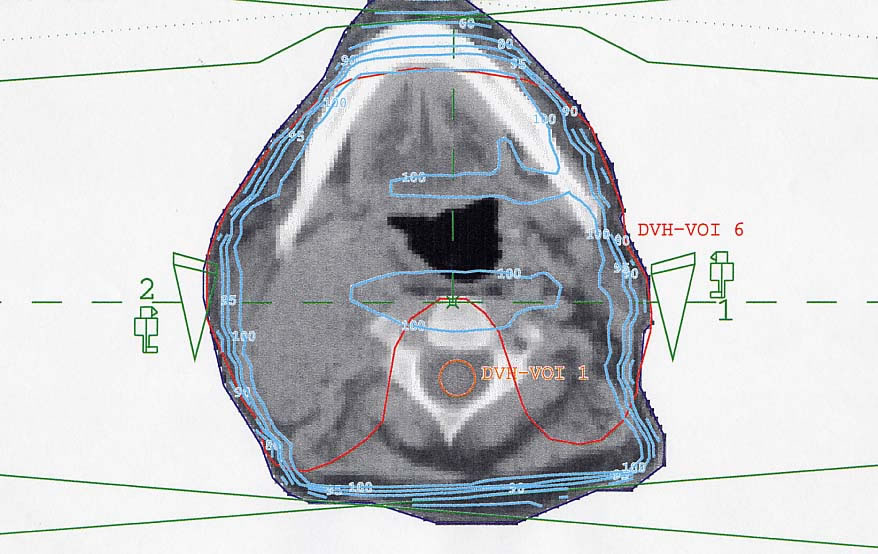

HNO-Karzinome: Bestrahlungsplan

Bestrahlungspläne